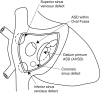

This review article will guide the reader through the basics of echocardiographic assessment of congenital left to right shunts in both paediatric and adult age groups. After reading this article, the reader will understand the pathology and clinical presentation of atrial septal defects (ASDs), ventricular septal defects (VSDs), atrioventricular septal defects (AVSDs) and patent arterial duct. Echocardiography is the mainstay in diagnosis and follow-up assessment of patients with congenital heart disease. This article will therefore describe the echocardiographic appearances of each lesion, and point the reader towards specific features to look for echocardiographically.